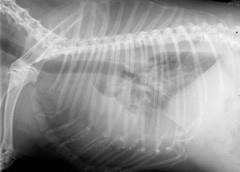

猫肺炎x光图片

猫肺炎x光图片,肺炎x光图片

盘点10张不可思议的猫咪x光片真相令人后怕

正常猫肺部x光片

猫x光片解读健康猫